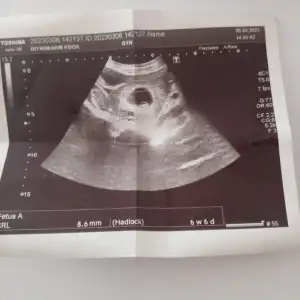

Kesenin görülmemesinden belliydi bi sıkıntı olduğu Allah razı olsun teşekkür ederimCanım vücut ne zaman atacağını biliyor yapabileceğin birşey yok malesef . Değer düşmeye başlayınca düşer diye düşünüyorum rabbim yardımcın olsun . Bir hafta bekle birşey olmazsa doktora gidersin seni zehirlemesin diye tedbir olarak ne bileyim belki bir mucize olur Allah'tan umut kesilmez![]()

Yolk kesesi de mi yoktuKesenin görülmemesinden belliydi bi sıkıntı olduğu Allah razı olsun teşekkür ederim![]()

Hiç birşey göremedi doktorYolk kesesi de mi yoktu

Anladım canım hayırlısı olsun rabbim daha sağlıklısını nasip etsin en azından hamile kalabiliyorsun demek ki artık daha kolay hamile kalırsın her şerrde vardır bir hayır rabbim hayrı görmeyi nasip etsinHiç birşey göremedi doktor

Yolk kesesi ne oluyoe ben hiç bilmiyorumYolk kesesi de mi yoktu